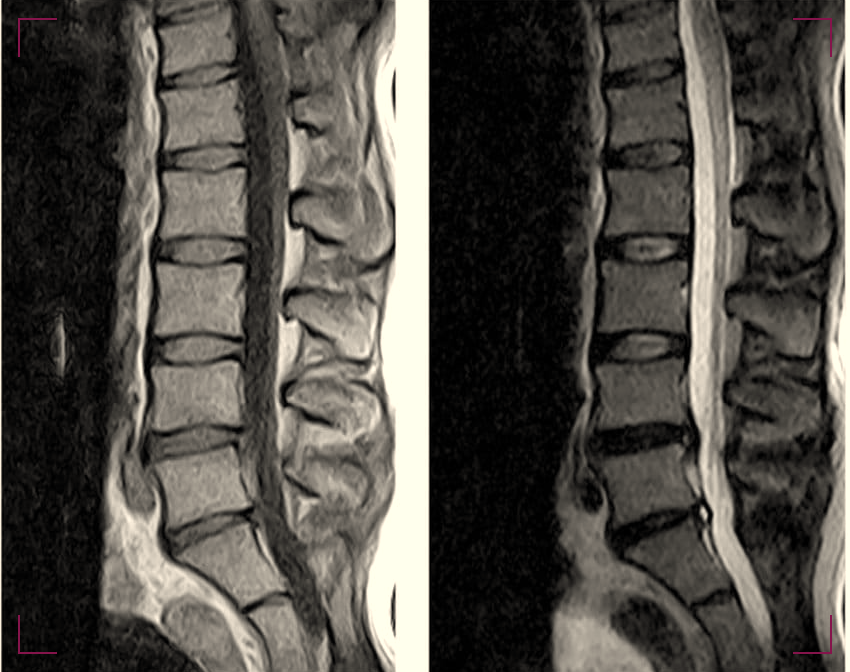

Imaging tests play a crucial role in confirming the diagnosis. Magnetic Resonance Imaging (MRI) is often the preferred method as it provides detailed images of both bone and soft tissues.

Computed Tomography (CT) scans and X-rays can also be utilized to assess the structural integrity of the vertebrae and discs.

A physical examination follows, during which the provider assesses spinal alignment, range of motion, muscle strength, and neurological function. Imaging studies such as X-rays, MRI scans, or CT scans may be ordered to visualize the structures of the spine and identify any abnormalities or degenerative changes.